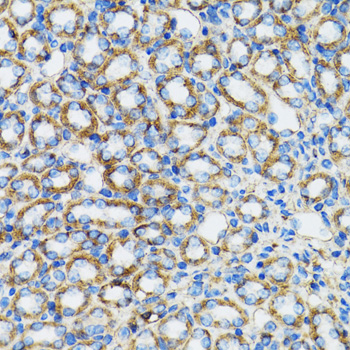

ApplicationWB, IHC, IP; Recommended dilution: WB 1:500 - 1:2000, IHC 1:50 - 1:200, IP 1:50 - 1:100